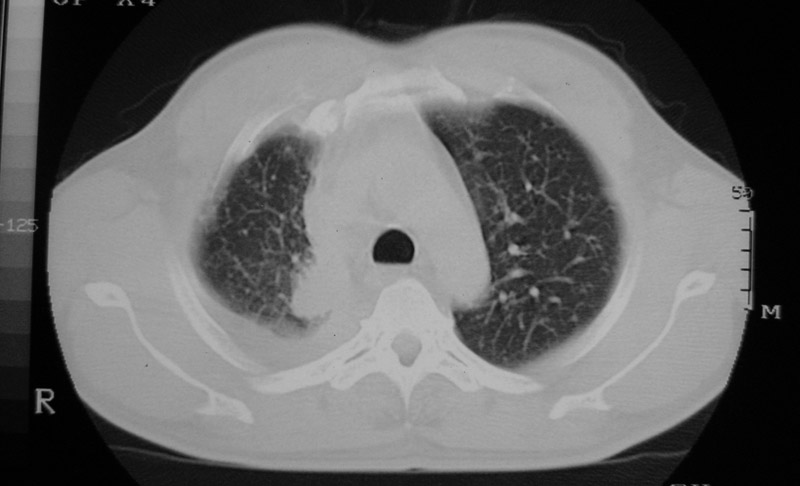

以下是引用守望可可西里在2006-9-11 15:29:00的发言:[br][br] ct平扫表现:右侧胸膜腔缩小,积液,胸膜增厚且不均匀、不规则,以纵隔胸膜增厚为主,边缘呈锯齿状,并见附壁内突之结节状肿块影。右肺含气量减少,纹理聚集,右肺门中下部见数个肿大的淋巴结。纵隔无移位,内未见明显肿大淋巴结,双侧主支气管以及各叶、段支气管比较通畅。。[br] 考虑:右侧胸膜恶性间皮瘤,伴肺门淋巴结转移。